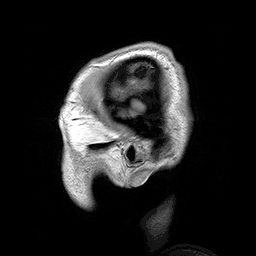

Neuroscience is a field devoted to the scientific study of the Nervous system. It is one of the most interdisciplinary scientific fields, and also one of the most rapidly advancing. Neuroscientists may come from a variety of backgrounds, including psychology, computer science, biology, and medicine. It advances the potential understandings of the humanities by offering hypotheses and conceptualizations for the underlying mechanisms of thought, emotion, behavior, and everything in between. Neuroscientists use an ever increasing range of tools, including scanners capable of showing brain activation in real-time, computer models that are capable of acquiring language capabilities using the same basic methodology of developing children, molecular techniques which can explain how changes on an infinitesimally small scale can translate into effects of incalculable gravity, and ethological studies which decode the complex workings and interactions of living creatures in their natural environments into overarching laws of behavior. From these studies they learn how the nervous system arises, comes to shape who we are, and even how it sometimes fails.